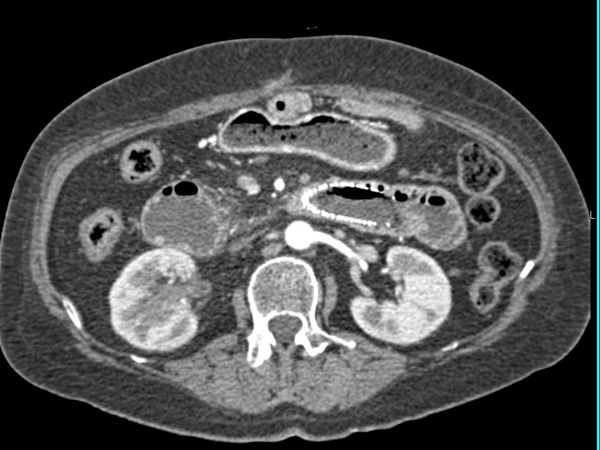

Для выявления заболевания доктор собирает анамнез и проводит осмотр слизистых оболочек и кожи. Основные лабораторные исследования, которые назначаются для диагностики рака ДПК: